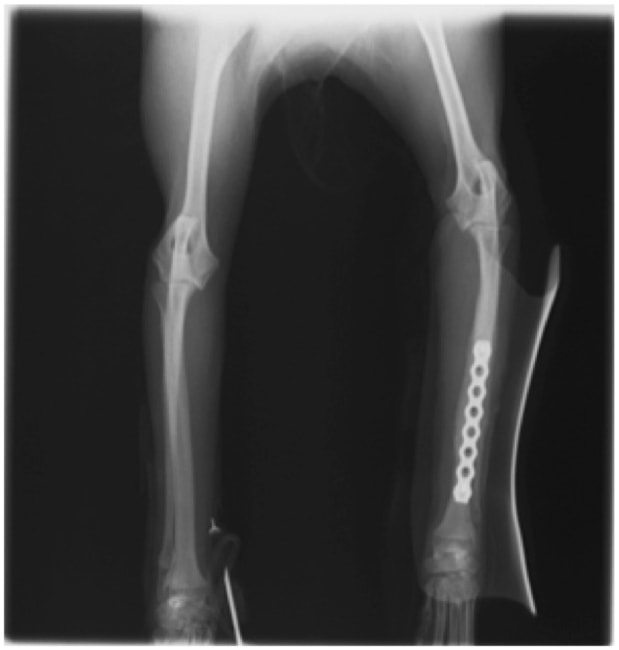

症例:交通事故による椎体脱臼

柴犬:9歳、避妊雌

交通事故直後、胸腰部に激しい疼痛、両後肢に完全麻痺を認め、シェフシェリントン徴候を呈していました。レントゲン検査において、第11-12胸椎間の脱臼が認められました。

脊髄の減圧、脊柱管の再構築・安定化を目的に、片側椎弓切除術およびMatrixMANDIBLE Plateによる椎体固定を実施しました。

隣接椎体を架橋するようにプレートを設置しました。

術後レントゲン写真